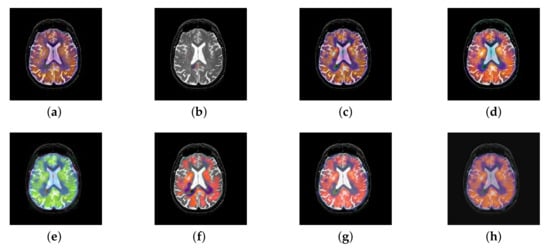

4.2. The Fusion of MRI-SPECT

SPECT image can absorb radionuclide distribution diagram from different directions in vivo and draw the distribution. Three-dimensional reconstruction diagram of radionuclides in each cross section in vivo after computer comprehensive processing. It is something that structural MRI does not have. So, the combination of the two could allow doctors to get more accurate physiological information.

In this section, there are four multi-modal image sets and each set is consist of MRI image and SPECT image that are corresponding to the sanme location slice of the brain as shown in Figure 7. Among them, Figure 7e,f are captured from patients who have suffered a subacute stroke. Figure 7a–d,g,h are captured from patients who have brain tumor. The fused images with different fusion methods based on DTCWT, NSCT, GFF, LPSR, IGM, DDcGAN, FusionCNN, and the proposed methods are shown in Figure 8, Figure 9, Figure 10 and Figure 11. It can be seen that the fused images obtained by LPSR and FusionCNN algorithm have serious color distortion. Based on DTCWT and NSCT algorithm, the fusion image structure information is not obvious. The fused images obtained by GFF and IGM algorithm contain almost no color information, which is not conducive for doctors to make correct diagnosis. The image obtained by the DDcGAN algorithm saves the color information in the SPECT to a great extent; however, the brightness of the fused image is too large, which causes the image to have no sense of hierarchy and the contrast to decrease. By comparing with other algorithms, we find that our algorithm has good color retention effect, clear structure information, moderate brightness, and no artifacts.

Figure 8.

Fused medical images obtained by different algorithms (Figure 7a,b): (a) dual tree complex wavelet transform (DTCWT), (b) guided filtering fusion (GFF), (c) non-subsampled contourlet transform (NSCT), (d) Laplacian pyramid sparse representation (LPSR), (e) internal generative mechanism (IGM), (f) Fusion convolutional neural network based (FusionCNN), (g) dual-discriminator conditional generative adversarial network based (DDcGAN), and (h) FusionNet.

Figure 9.

Fused medical images obtained by different algorithms (Figure 7c,d): (a) DTCWT, (b) GFF, (c) NSCT, (d) LPSR, (e) IGM, (f) FusionCNN, (g) DDcGAN, and (h) FusionNet.

Figure 10.

Fused medical images obtained by different algorithms (Figure 7e,f): (a) DTCWT, (b) GFF, (c) NSCT, (d) LPSR, (e) IGM, (f) FusionCNN, (g) DDcGAN, and (h) FusionNet.

Figure 11.

Fused medical images obtained by different algorithms (Figure 7g,h): (a) DTCWT, (b) GFF, (c) NSCT, (d) LPSR, (e) IGM, (f) FusionCNN, (g) DDcGAN, and (h) FusionNet.